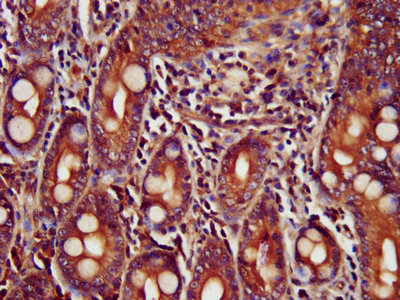

IHC image of CSB-PA892166LA01HU diluted at 1:400 and staining in paraffin-embedded human small intestine tissue performed on a Leica BondTM system. After dewaxing and hydration, antigen retrieval was mediated by high pressure in a citrate buffer (pH 6.0). Section was blocked with 10% normal goat serum 30min at RT. Then primary antibody (1% BSA) was incubated at 4°C overnight. The primary is detected by a biotinylated secondary antibody and visualized using an HRP conjugated SP system.